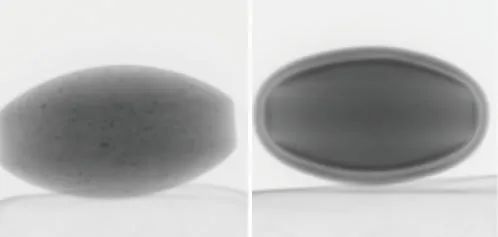

在本例中,觀察到兩種具有不同結(jié)構(gòu)的片劑(片劑A和B)(圖2)。片劑的透視圖像如圖3所示。

片劑A (左) 片劑B(右)

圖3 片劑透視圖